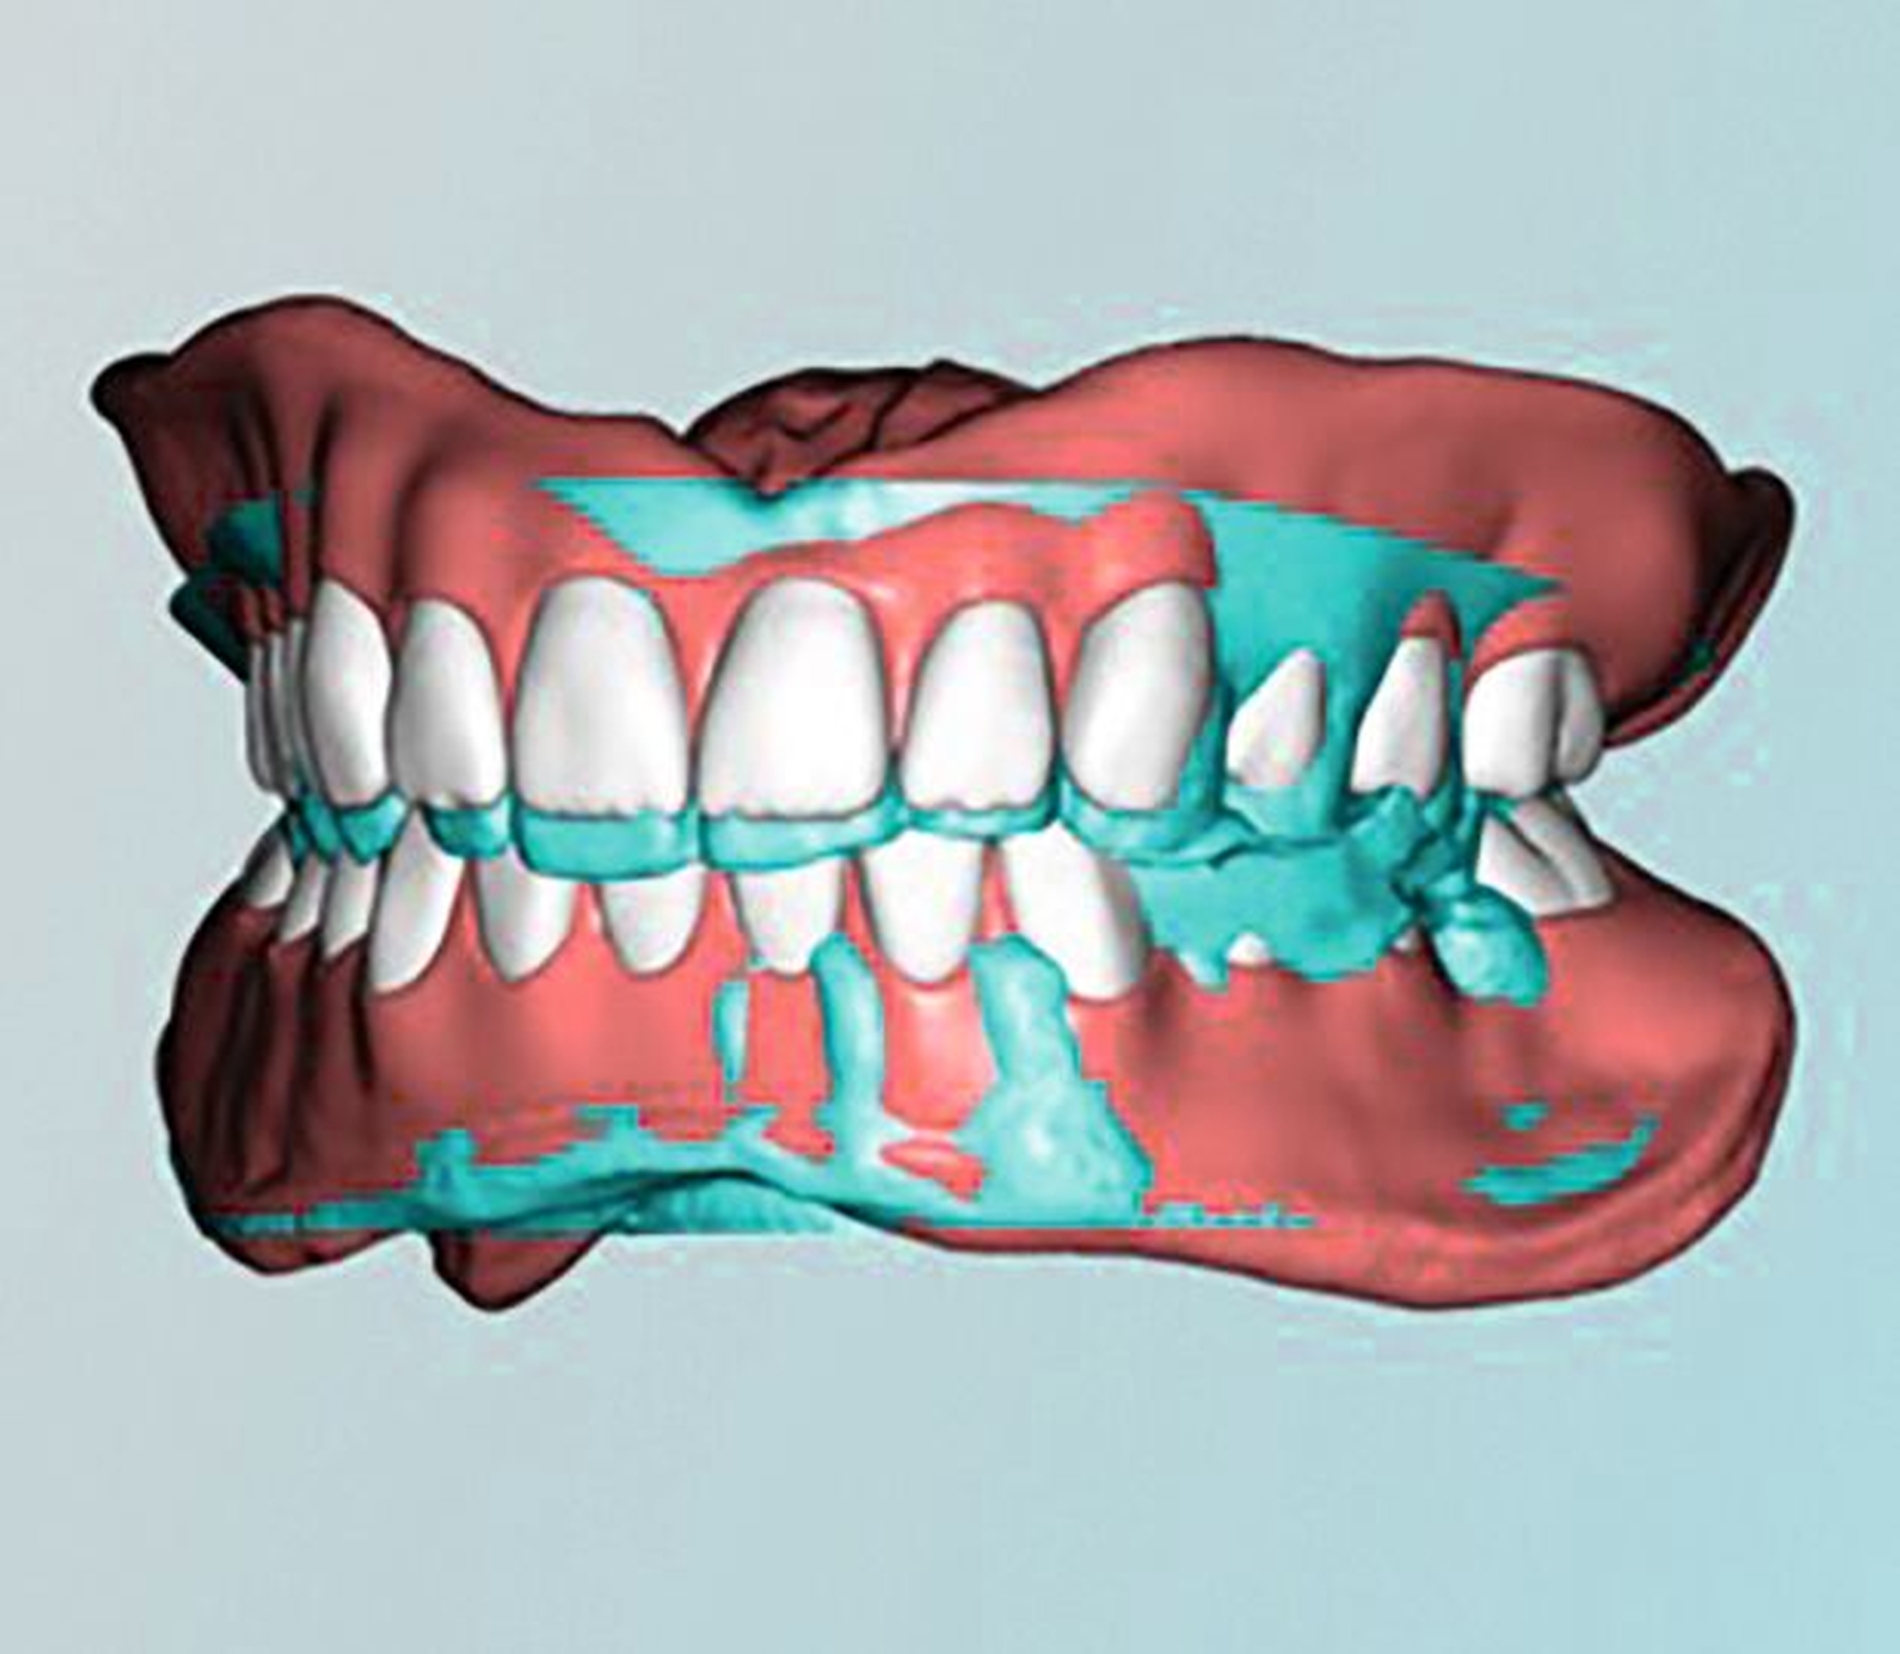

Bei Totalprothesen lässt sich dies beispielsweise durch die Replicadenture-Technik umsetzen. Die digitale Technologie hat dieses Verfahren nochmals vereinfacht. In der ersten Behandlungssitzung wird der bestehende Zahnersatz auf seine Mängel geprüft. Diese werden soweit möglich provisorisch am Zahnersatz korrigiert beziehungsweise an diesem markiert (Abbildung 9). Hierzu gehören der Aufbau der Stützkontakte und/oder die Registrierung der Prothesen in regelrechter Kieferrelation, die Ausformung und Anpassung der Prothesenränder und -basis ans Tegument, die Kennzeichnung der Lage der mittleren oberen Schneidezähne, aber auch die Übertragung der regelrechten Ausrichtung der Kauebene. Der so umgestaltete Zahnersatz kann mittels Intraoralscanner digitalisiert oder ins Labor zum Scannen gegeben werden. Nach der Informationsaufnahme werden die provisorischen Veränderungen wieder entfernt und der Patient erhält seinen unversehrten Zahnersatz zurück. Im Labor kann anhand der Datensätze der optimierten Prothesen ein neuer Zahnersatz konstruiert werden. Dieser sollte gegenüber dem alten Zahnersatz nur so viel Veränderung wie nötig aufweisen, damit eine einfache und schnelle Adaptation gelingt. In der zweiten Behandlungssitzung können die neuen Prothesen im Idealfall bereits eingesetzt werden.